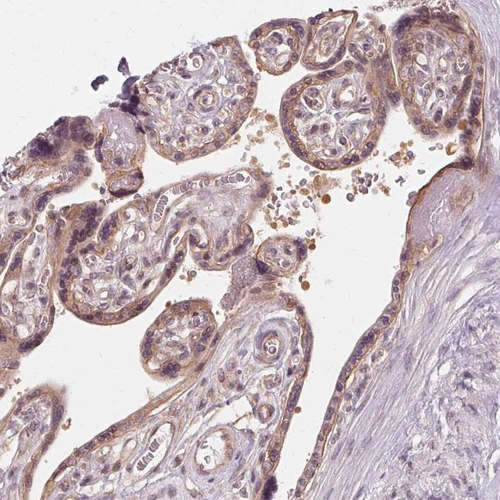

Immunohistochemical staining of human testis shows moderate cytoplasmic positivity in cells in seminiferous ducts.